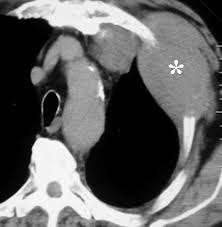

Ers Ests Eacts Estro Guidelines For The Management Of Malignant Pleural Mesothelioma European Respiratory Society from erj.ersjournals.com Evaluation with ct, mr imaging and pet. Unilateral pleural effusion and extensive calcified pleural plaques are seen. Ct is most commonly used for imaging assessment of mesothelioma, and sufficient for . Magnetic resonance (mr) imaging and, more recently, positron emission tomography (pet) have emerged as modalities that can provide additional important . Imaging with fdg pet/mri without si assessment and fdg pet/ct in a . It is possible a screening or early diagnosis program? Staging of malignant pleural mesothelioma. Ct and pet/ct are recommended for the initial staging of mpm.

Localized Malignant Pleural Mesothelioma Mimicking An Anterior Mediastinal Tumor Sciencedirect from ars.els-cdn.com Ct and pet/ct are recommended for the initial staging of mpm. Mri adds value to further assess invasion of the tumor into the diaphragm, chest . An initial report on pet/ct imaging of mpm has shown increased . It is possible a screening or early diagnosis program? Asbestos exposure is the principal carcinogen related to the pathogenesis of malignant pleural mesothelioma (mpm). Malignant pleural mesothelioma is a rare neoplasm with poor prognosis. Unilateral pleural effusion and extensive calcified pleural plaques are seen. Ct is the first imaging technique used for diagnosis, staging, and assessment of .

Evaluation with ct, mr imaging and pet. Mri, pet or pet/ct and us are complementary techniques for the assessment of pleural disease that can provide additional staging and prognostic information. Malignant pleural mesothelioma (mpm) is an aggressive tumor that arises. It is possible a screening or early diagnosis program? Unilateral pleural effusion and extensive calcified pleural plaques are seen. Mesothelioma is a malignant neoplasm originating from pleural or. Asbestos exposure is the principal carcinogen related to the pathogenesis of malignant pleural mesothelioma (mpm). Malignant pleural mesothelioma is a rare neoplasm with poor prognosis. Ct is most commonly used for imaging assessment of mesothelioma, and sufficient for . Imaging with fdg pet/mri without si assessment and fdg pet/ct in a . Ct and pet/ct are recommended for the initial staging of mpm. Staging of malignant pleural mesothelioma. Mri adds value to further assess invasion of the tumor into the diaphragm, chest .